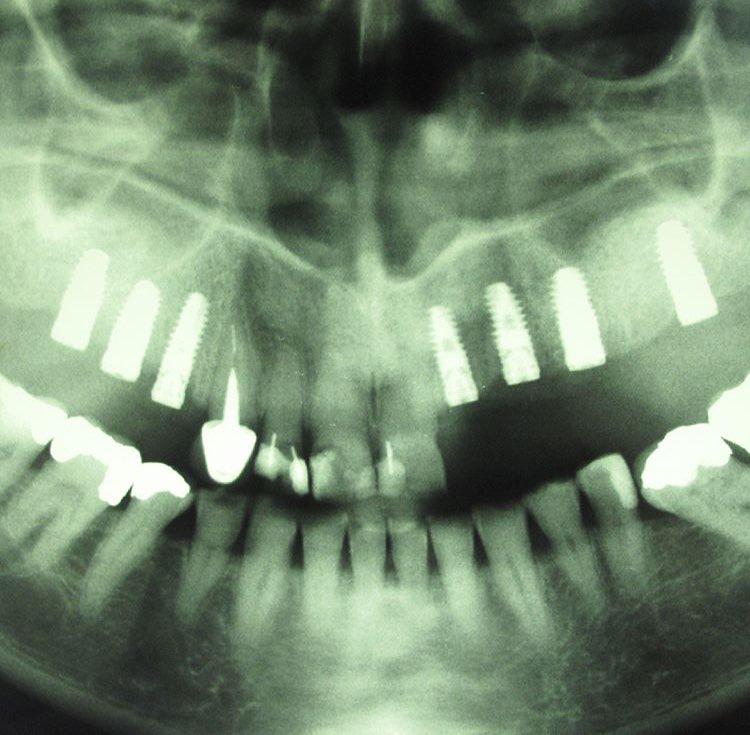

جراحی گذاشتن ایمپلنت های دندانی جهت جایگزینی دندانهای از دست رفته

گذاشتن ايمپلنت همزمان با كشيدن دندان

جراحی پیوند استخوان جهت افزایش میزان استخوان و آماده سازی برای گذاشتن ایمپنت

جراحی سینوس لیفت بصورت باز و بسته برای گذاشتن ایمپلنت

ایمپلنت مجموع قطعاتی است که با جراحی داخل فک ثابت میشوند روی آن دندان مصنوعی قرار میگیرد و در نهایت ظاهری مشابه با دندان طبیعی پیدا میکند.

بهطور کلی برای گذاشتن ایمپلنت دندان چندین مرحله باید انجام شود تا قطعات تشکیل دهنده در کنار یکدیگر قرار گیرند و بیمار بتواند به جای دندان طبیعی از آن استفاده کند. ایمپلنت از نظر ظاهری مشابه دندان طبیعی است و در دهان همان حس طبیعی را برای جویدن القا میکند و سوء هاضمه ایجاد شده بر اثر ناتوانی در جویدن غذا را برطرف مینماید.

ایمپلنت دندان برای جایگزین کردن یک یا چندین دندان از دست رفته کاربرد دارد و میتواند برای تمام دندانها به صورت ثابت یا متحرک استفاده شود. در هر دو حالت فوق کلمه ایمپلنت استفاده میشود اما حالت دوم بیانگر معنی واقعی ایمپلنت است و به مجموعهای از قطعات ایمپلنت گفته میشود و هر کدام از قطعات به تنهایی نام و کارایی مجزایی دارند.